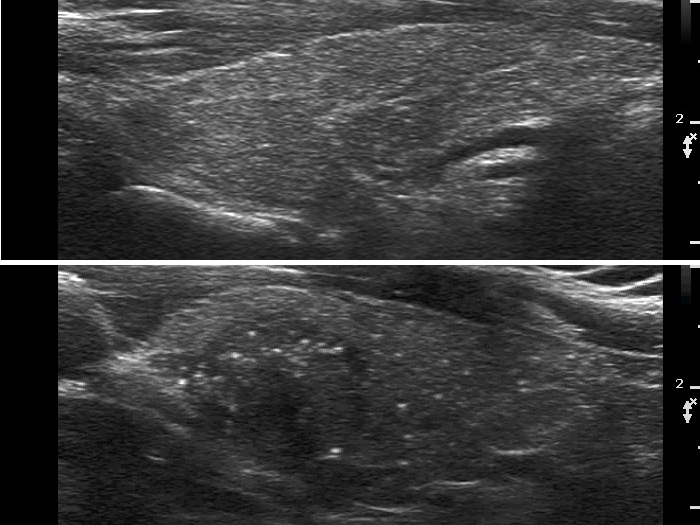

100 consecutive cases of papillary cancer - case 076 (ultrasonographic picture 14)

Comparison of the right lobe (upper) presenting fibrotic changes with the left lobe (lower) showing numerous microcalcifications. Note the difference between the size of the hyperechoic granules caused by fibrosis and microcalcifications.